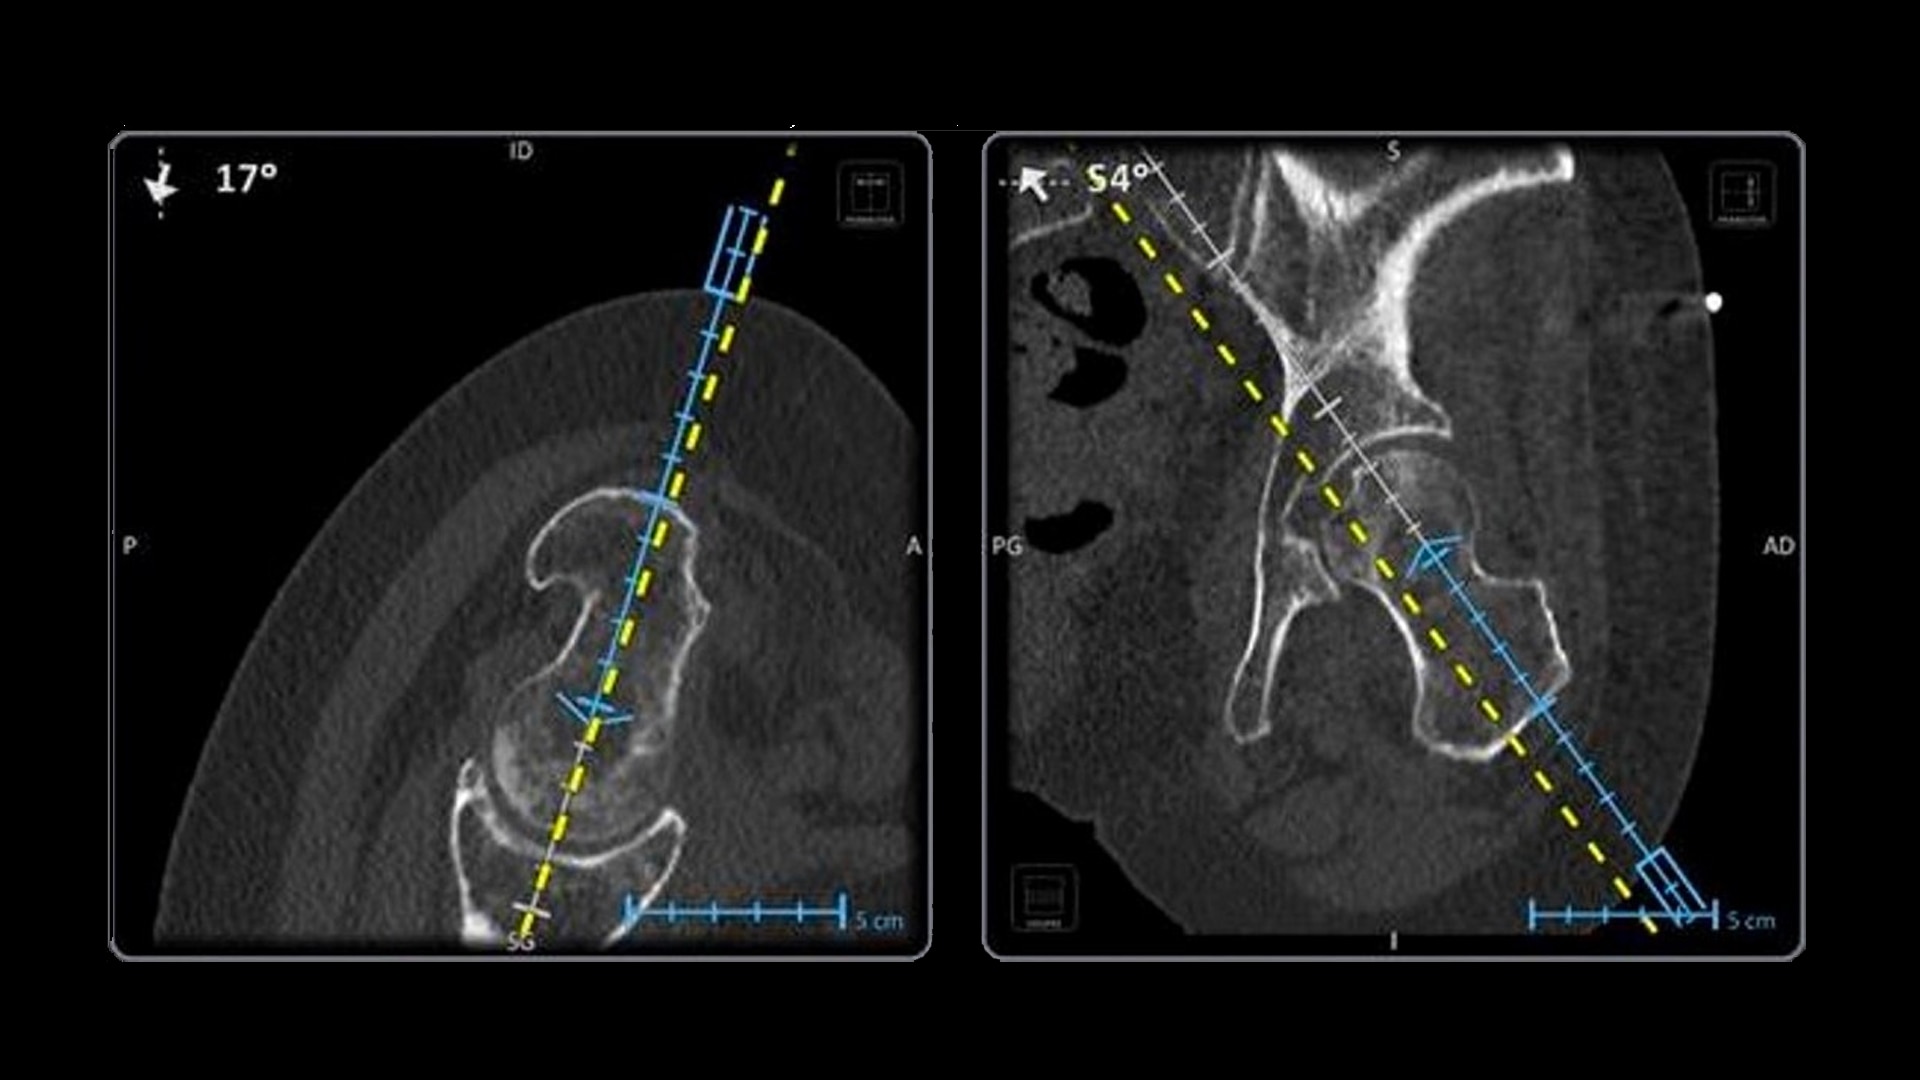

Accuracy

Improve accuracy to reach target and avoid critical structures and organs¹

Versatility

Ideal to use with various percutaneous interventions² with various complexity